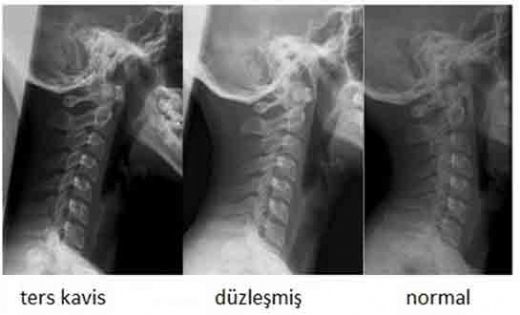

Boyun kemiği, insan vücudunun en önemli yapı taşlarından biri olup, birçok kritik görevi yerine getirmektedir. Bu makalede, boyun kemiğinin anatomik yapısı, işlevleri ve sağlığına dair önemli bilgiler ele alınacaktır. Anatomik Yapı Boyun kemiği, servikal vertebra olarak bilinen yedi ayrı omurdan oluşmaktadır. Bu omurlar, C1'den C7'ye kadar numaralandırılır. İlk iki omur, atlas ve aksis olarak adlandırılır ve başın hareketini sağlamak için özel yapılandırmalara sahiptir.

Bu omurlar, intervertebral diskler ile birbirinden ayrılır ve boyun bölgesine esneklik sağlar. Ayrıca, boyun kemiği çevresinde bulunan kaslar, bağlar ve sinirler, hareket ve duyusal işlevleri destekler. Boyun Kemiğinin Fonksiyonları Boyun kemiği, birçok önemli işlevi yerine getirmektedir. Bu işlevler arasında: